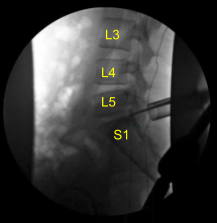

A 22-gauge spinal needle was used to localize the L5-S1 level. A marking pen was used to demarcate the midline. An 18 mm vertical incision adjacent to the spinous process on the right side was demarcated. 1% lidocaine with epinephrine was infused.

The skin was opened with a #15 blade scalpel. Hemostasis was obtained with Bovie. Bovie was used to sharply divide the fascia. Sequential dilators were used to dock a 16 mm diameter x 4 cm tubular retractor which was affixed rigidly to the bed frame.

The herniated disc fragments were collected and sent to pathology for analysis. An annular defect was identified and extended with a bayoneted #15 blade scalpel.Neurolysis was performed with micro instruments of the S1 nerve root enabling sufficient retraction to fully remove the multiple herniated disc fragments until circumferentially the S1 nerve root was completely decompressed as well as the ventral thecal sac. This was confirmed with nerve hooks, Penfield micro instruments and fluoroscopy.